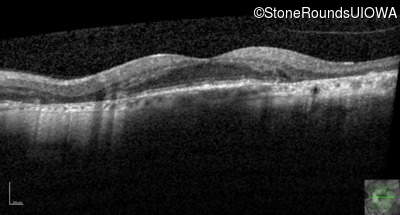

Age at visit: 51 years

This 51 year old woman first experienced some abnormality in her distance vision when she was 27 years old. She feels that her vision has been stable since that time.